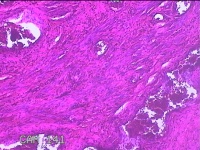

阴道后壁组织

性别

女

年龄

44岁

临床诊断

阴道前后壁膨出Ⅱ度

一般病史

分娩厚19年,阴道肿物膨出2月,加重3周。

标本名称

大体所见

灰白粉红色组织4.5x2.8x0.7cm一块,表面糜烂,切面灰白粉红色,质软。